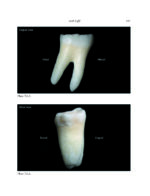

THE MANDIBLE: An Atlas Osteological and Radiological Anatomy 2022

کتاب افست و اطلس رنگی و ارزشمند”THE MANDIBLE: An Atlas Osteological and Radiological Anatomy 2022 ” ویرایش اول